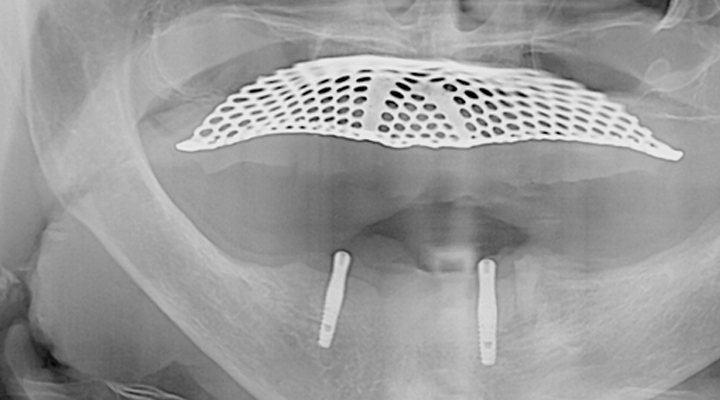

여러 개의 임플란트를 심은 뒤, 그 사이를 금속 막대로 연결해 튼튼한 지지대를

만들고, 그 위에 틀니를 안정적으로 고정하는 방식입니다.